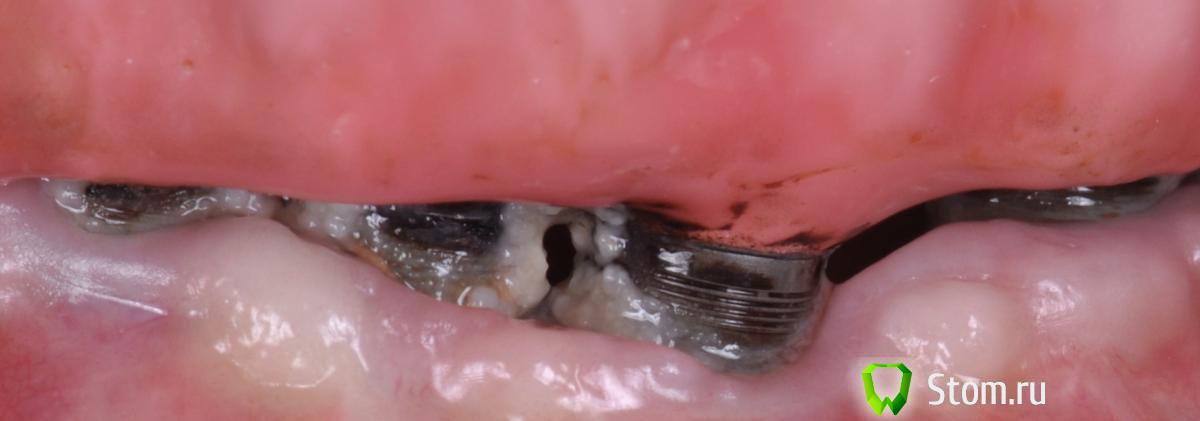

doctore Опубликовано 15 января, 2012 Поделиться Опубликовано 15 января, 2012 (изменено) уфф....самое сложное - принять адекватно-взвешенное решение.Сложно сказать. Но, если процитировать какого то гуру ( не помню кто конкретно) :если вы имеет проблему на своем имплантате- вы будете его лечить и спасать до последнегоесли на чужом- то естественно удаление и новый винт)На своем,конечно.И как спасать или лечить?Вопрос к теме фиксации.Тактик то немного.Вот ,например,в таком случае. Изменено 15 января, 2012 пользователем doctore Ссылка на комментарий

doctore Опубликовано 15 января, 2012 Поделиться Опубликовано 15 января, 2012 (изменено) а смысл снимать? в данном случаеФото наверху прикрепил-уже после твоего ответа.А что делать-ждать? Изменено 15 января, 2012 пользователем doctore Ссылка на комментарий

doctore Опубликовано 15 января, 2012 Поделиться Опубликовано 15 января, 2012 Вычистить и обработать винты можно и не снимая. По крайней мере тут.А смысл чистить? Ну хватит на пару недель-месяц.Согласись,единственный способ-заполировать по периметру всю визуально видимую часть от резьбы.Хуже уже не будет.А в таком виде,как на фото внизу,делать это гораздо удобней Ссылка на комментарий